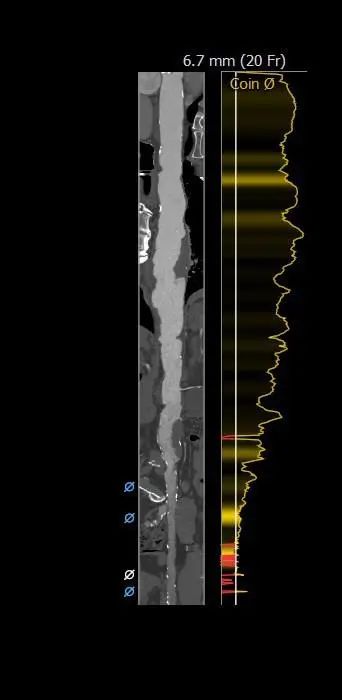

外周分析

• 该患者外周多发附壁血栓,合并胸主、腹主及髂总动脉瘤,动脉瘤巨大,并且内由附壁血栓,经股动脉行TAVR手术血管并发症风险极高。测量发现双侧锁骨下动脉内径可,预计采用左锁骨下动脉为主入路,右股动脉为辅入路。

1.根据术前测量分析,采取左侧锁骨下动脉微创2厘米切开,作为主入路,右股为辅入路。